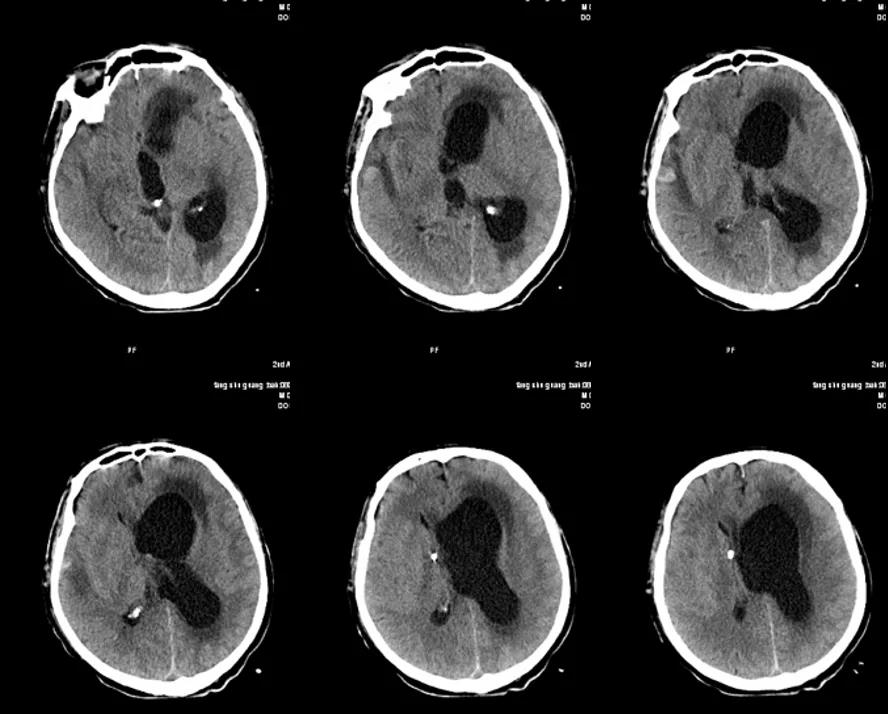

3月3日考虑药物热不能除外暂停威凡针,改予卡泊芬净针50 mg静滴QD,停泰能针,改马斯平针1 g静滴q8h。3月3日患者癫痫大发作一次,持续1分钟,发作后意识恢复。急查CT未见明显异常(图7)。

图7. 3月3日头颅CT

患者颅内感染明确,但仍缺乏病原学依据。抗生素方案调整为美罗培南针联合替加环素及斯沃针。后患者意识水平进行性下降,头颅MRI复查提示脑积水进行性加重。3月27日复查腰穿测压290 mmH₂O,脑脊液淡黄透明澄清。神经外科会诊后3月28日行右侧ommaya囊植入术并予穿刺引流,术后CT复查(图10):右侧额叶少量硬膜下积液,右侧脑室相对缩小,左侧脑室及第三脑室扩张,中线结构右偏。

图10. 3月29日头颅CT

ommaya囊穿刺引流液通畅,为无色清亮脑脊液,但反复送培养及涂片均阴性。4月9日患者出现意识障碍加重,心率增快达150次/分,深大呼吸,血压175/116 mmHg,双侧瞳孔直径3 mm,对光反射迟钝,立即予以20%甘露醇250 ml静脉输液,紧急气管插管,呼吸机辅助呼吸。复查头颅CT(图11)提示左侧侧脑室及第三、四脑室明显扩张,中线结构局部右偏。

图11. 4月9日头颅CT

4月10日术后CT复查:左侧脑室及右侧颞叶出血灶,脑室扩大(图12)。

图12. 4月10日头颅CT